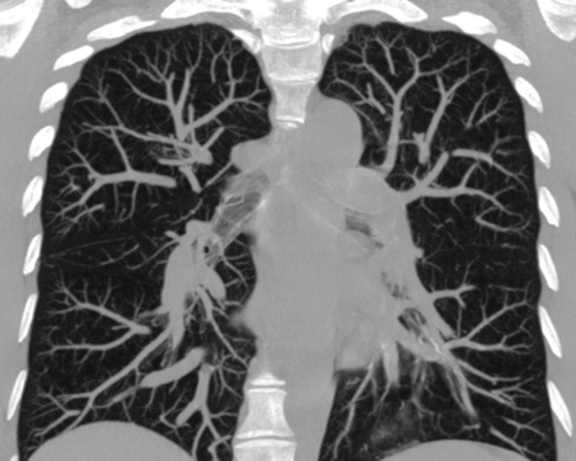

Исследование проводится только по направлению специалиста. Во время КТ органов грудной полости (легкие, средостения, грудная стенка, сердце (обзорно), лимфатические узлы, позвоночник в зоне визуализации) происходит сканирование до контрастирования и после введения йодсодержащего контрастного препарата.

Показания для проведения данного вида КТ: заболевания, в том числе и новообразования органов грудной полости.